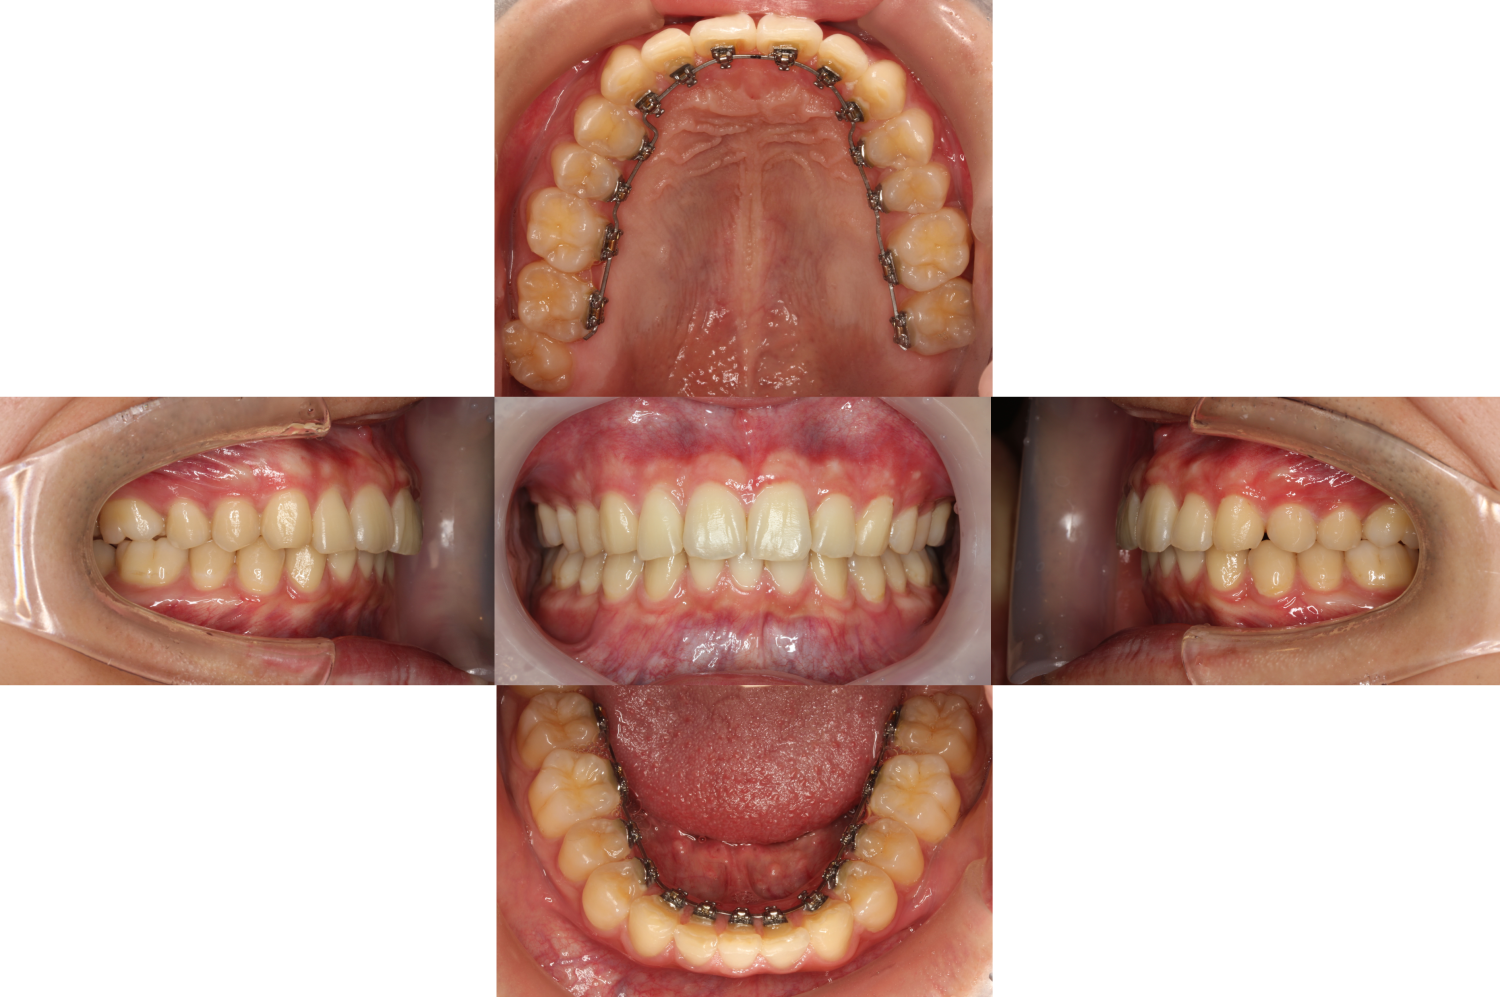

初診時

過蓋咬合・裏側矯正の症例

初診時の口腔内です。

【凸凹、上の歯が出ている、上下の歯が噛み合わない】等をお悩みでカウンセリングにいらっしゃいました。

また、こちらの患者様は先天的に右下の二番目の歯が欠損しています。

【欠損歯】は珍しくなく、他の患者様と同様に・患者様のお悩み・骨格・お顔・歯のバランス等を分析してその患者様に合った矯正治療を行います。